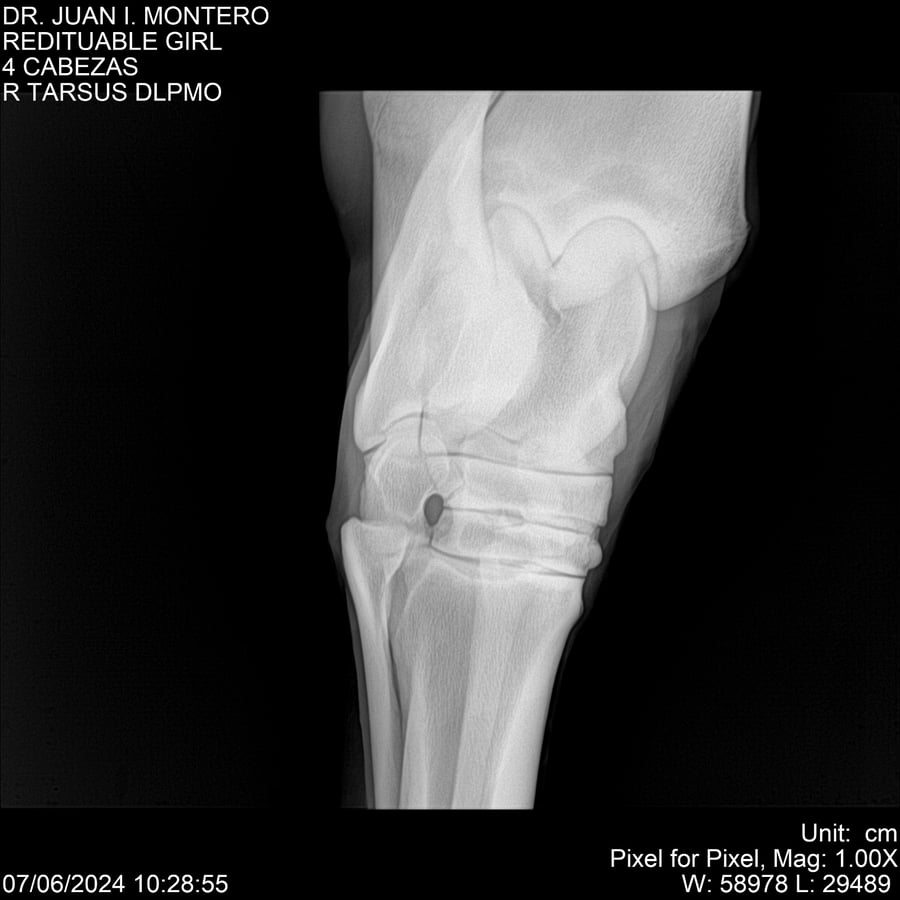

LOTE 19, REDITUABLE GIRL Lote Anterior Volver al remate Lote Siguiente Ficha Contacto Montevideo - Ficha del Lote Identificador: #281096 Categoría: Yeguarizos Montevideo - 79 Visualizaciones ClicData Contacto Empresa: Abelenda N. R., Walter Hugo Nombre*: Teléfono* : E-mail* : Mensaje Enviar Registrese gratis Este contenido Exclusivo está disponible sólo para usuarios registrados Ingresar